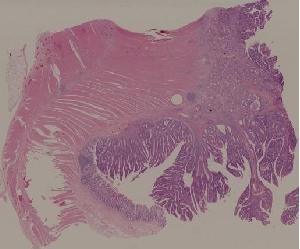

29.结肠腺癌

低倍视野